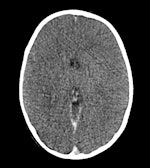

He emphasized that after a period of time, all corpses will display evidence of gas emboli. Previously it was believed this condition was a signature of cause of death for divers who experienced rapid changes in pressure, but Gorincour showed that this conclusion can only be made if the examination takes place within three hours of the accident, and that the window closes after six hours. He has also found that subcutaneous emphysema, or air trapped in tissues under the skin, can be caused by efforts to resuscitate a drowning victim and cannot always be attributed to a drowning accident.